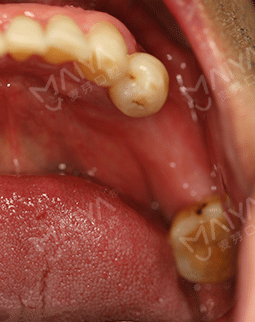

按照预约的时间,今天早早就来到了麦芽口腔,通过德国KAVO锥形束CT检查缺牙处牙槽骨的骨质密度、厚度,并分析牙周口腔健康后,郑院长根据我牙槽骨数据和口腔健康情况分析,采用MAC数字化精确种植,来恢复牙咬合功能的种植方案。

首先通过数字化精确影像采集测量患者牙床的骨质密度、牙槽骨本身的高度、宽度等条件,设计最佳力学种植点,同时发现神经血管,做到心中有数。在手术过程中,通过实时导航技术,控制种牙的深浅、避开口内危险区域,不仅减小了创口,平均种1颗牙耗时10分钟,减少了肿痛和出血量,缩短了种植牙时间,种植位置更准确,种植成功率更高,帮助了无数害怕疼痛的缺牙患者,轻松拥有一口好牙。